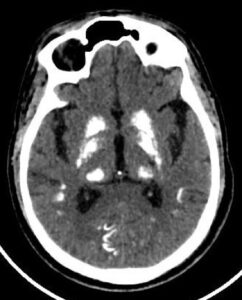

CASE 6- FAHR’S DISEASE

Near symmetric patchy calcifications are seen in bilateral cerebral and cerebellar hemispheres including:

- Dentate nuclei